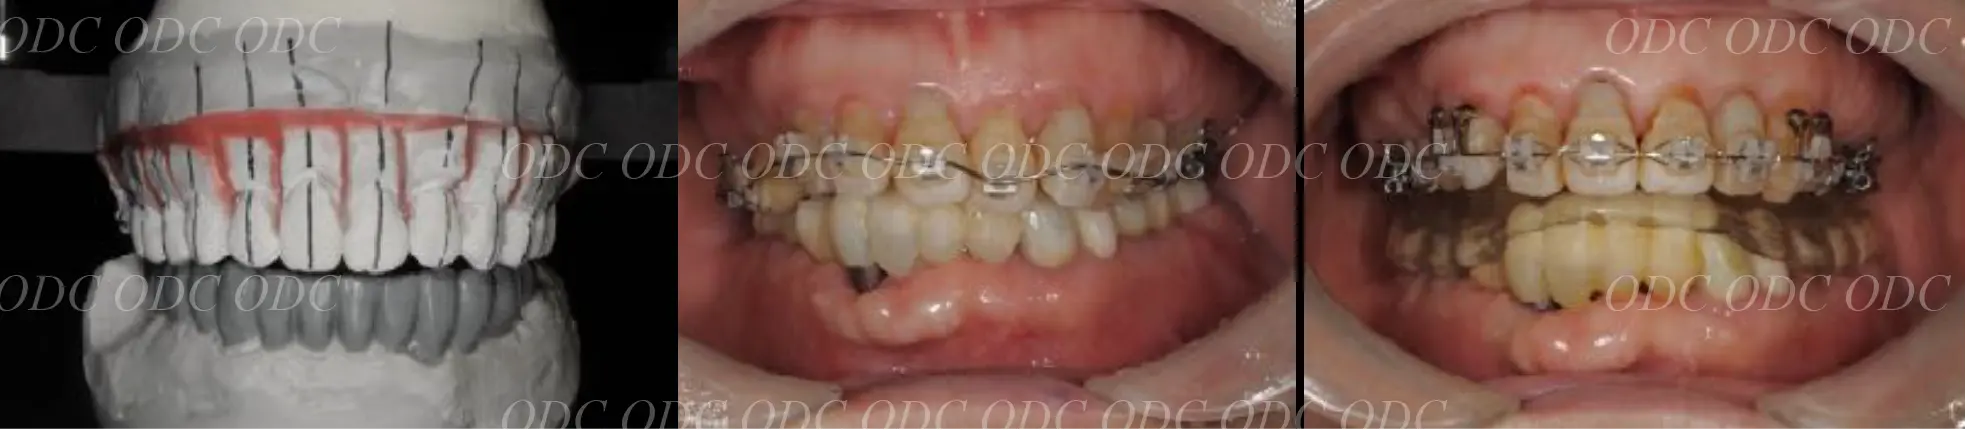

前歯がもともと4本、生えてこなかった症例。

インプラント治療を希望。

顎位(噛み合わせ)を正し、矯正治療にて歯を移動させる。

コンピューターで計画を行い、上部構造に関してもコンピューターにてデザイン。

最終物が装着されるまでに第1のプロビジョナルレストレーション(上段)と第2のプロビジョナルレストレーションを装着。

最終の補綴物が装着された、口腔内写真とレントゲン写真。